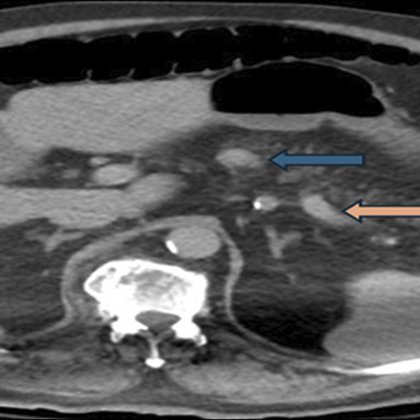

Thrilled to share that our case report has been published!!! @ACGCRJ - Successful Endoscopic Ultrasound-Guided Radiofrequency... : ACG Case Reports Journal https://t.co/k5AykfTrMV EUS-guided RFA—and the rapidly growing field of EUS-based interventions continues to reshape

ncreatic body mass confirmed as a World Health Organization grade 1 insulinoma on histopathology. Given the high surgical risk, we performed a EUS-RFA with 13 sequential ablations. Blood glucose...